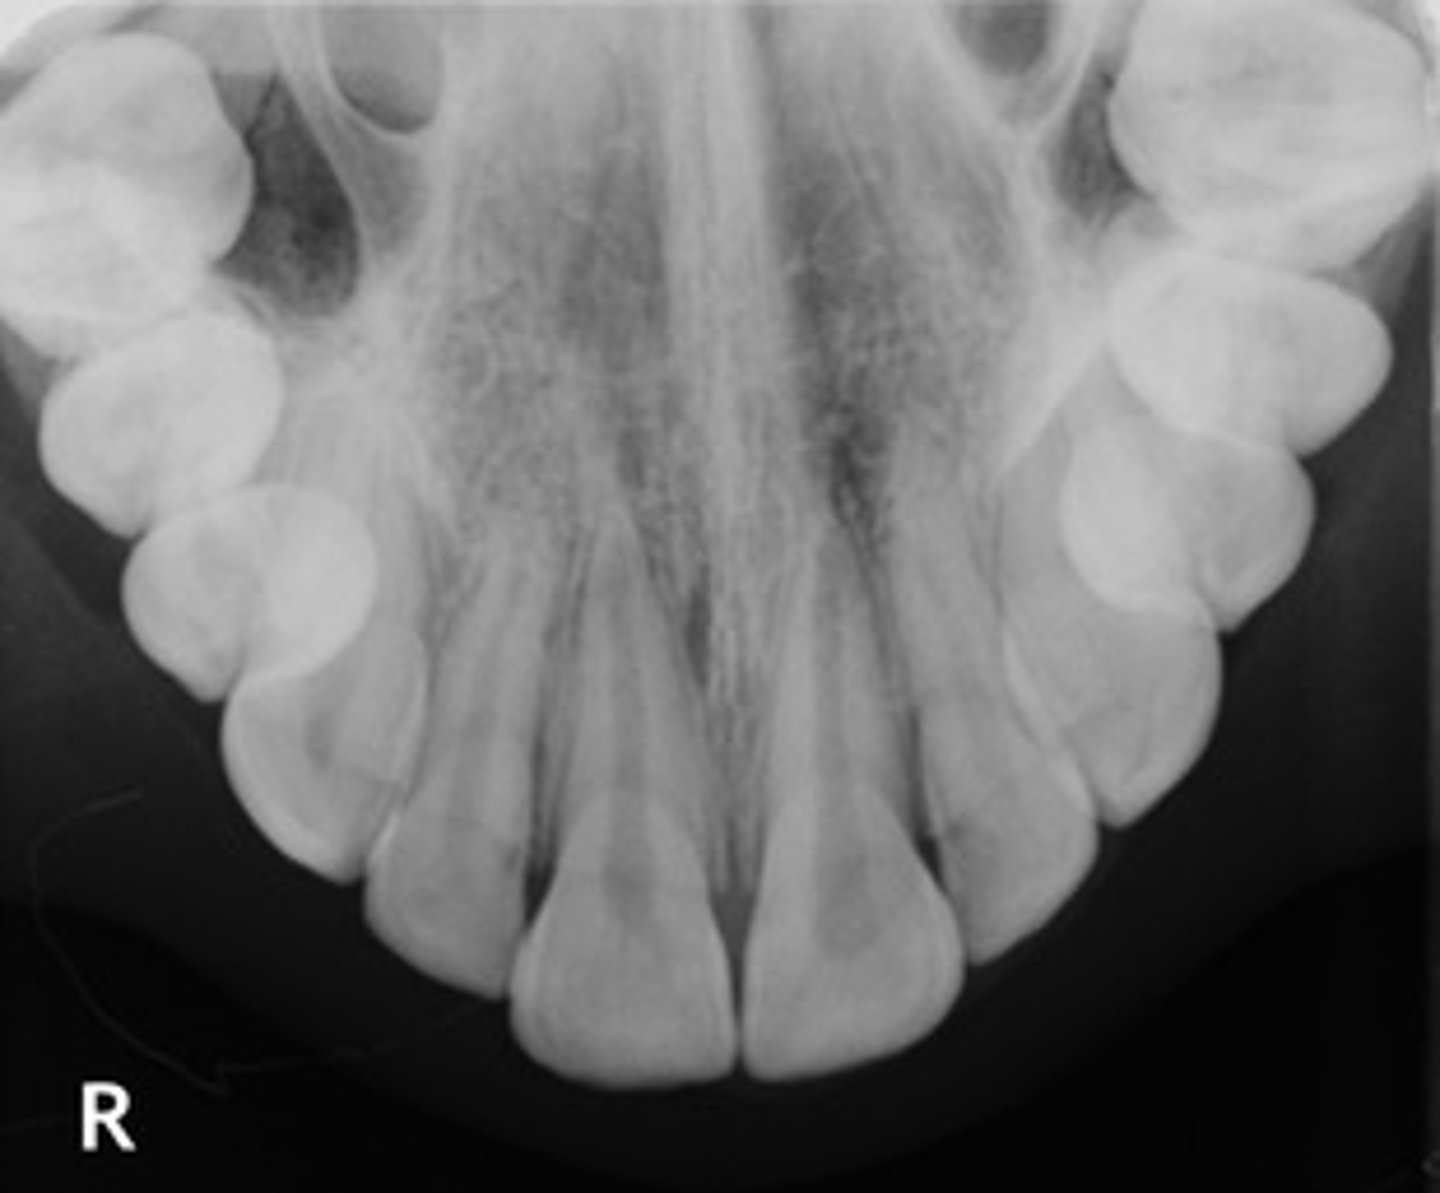

periapical

radiographic image showing the crown, root tip, & surrounding structures

any abnormalities of the root structure & surrounding bone structure